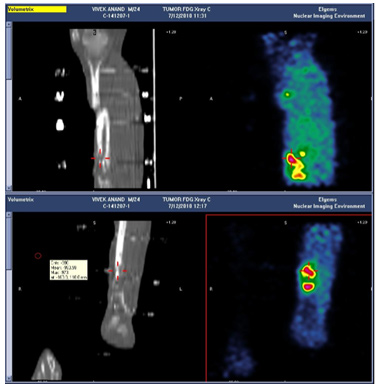

She was asked to get a scan done, and when she came to the scan center which is in the same building she apparently saw the CLLR board which specifically lists infection/osteomyelitis as one of our areas of expertise, and has a line "Cutting edge techniques tempered by 25 years of experience".

That prompted her to seek our opinion.

After reviewing her history, reviewing her xrays and examining her, we sat her down (along with husband and a couple of relatives) and discussed the options before her.

She seemed to have a 'wrist drop' which I thought was more because of adhesions or the inflamation within the compartment, rather than a problem with the radial or posterior interosseous nerve.

The only option really in my opinion was to do a proper debridement, clear the infection and then think of the reconstructive aspect.

In May 2011, we did the surgery for her and the plan was to do a thorough debridement, use local antibiotic in Calcium Sulphate pellets (Stimulan), and stabilise.

The debridement and the antibiotic pellets was the 'easy' part. How to stabilise a large defect (for I was pretty sure that was what we were going to have at the end of debridement.

|

| Central diaphysis of the Radius and Ulna sequestrated |